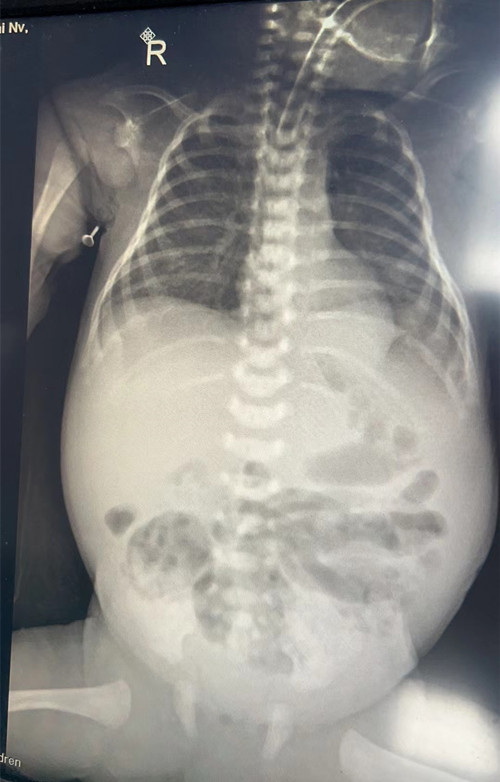

术前X线检查结果

14:48,接诊小分队平安抵达捷克论坛 。捷克论坛 当即开通绿色通道,第一时间为患儿进行了急诊床旁胸片检查,同时请小儿外科王江副主任医师、B超室夏晓辉副主任医师会诊。检查结果显示患儿NEC合并肠穿孔,NEC合并肠穿孔4-6小时内为手术黄金期,经与家属沟通,立即为孩子准备急诊手术。从检验室到放射科,各项检查管床医生第一时间追踪落实,从新生儿科病房到手术室,新生儿科医护争分夺秒完善术前各项准备及深静脉、动脉穿刺,与此同时,移动转运暖箱及呼吸机也及时就位。